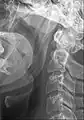

Le ligament stylo-hyoïdien contient fréquemment un peu de cartilage en son centre. Celui-ci peut s'ossifier, allonger l'apophyse styloïde et entraîner un syndrome d'Eagle.

Ligament stylo-hyoïdien ossifié ou processus styloïde allongé.